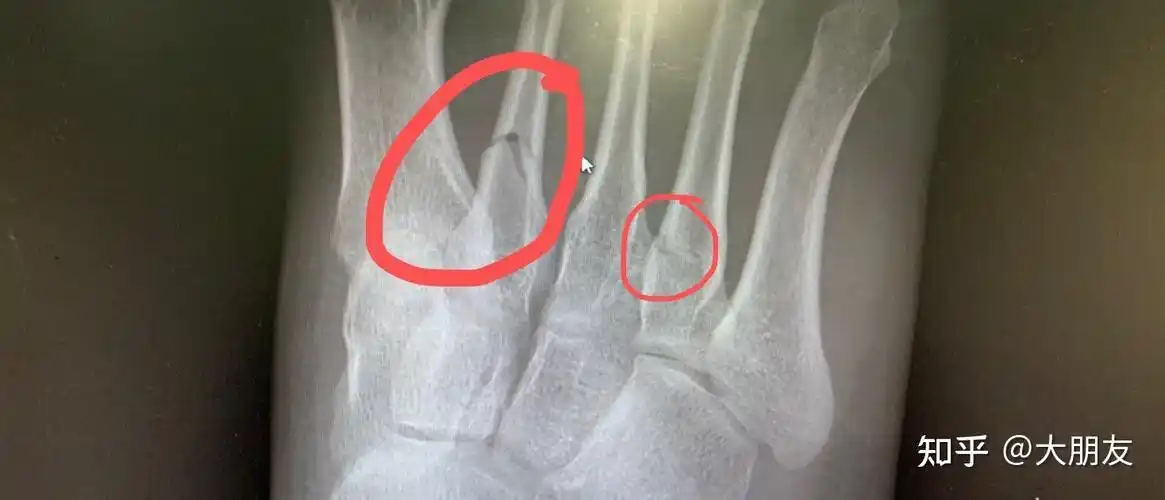

右脚第二第四跖骨(脚趾骨)骨折0101